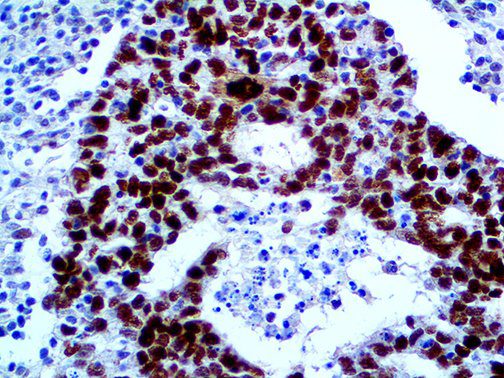

It is the ICU physician who is most likely to witness one of the deadliest manifestations of the abnormal immunological response, the cytokine storm syndrome (CSS). This response is also referred to by some as the cytokine release syndrome (CRS). CSS is characterized by continuous activation and expansion of macrophage and lymphocyte populations, which secrete large amounts of cytokines, causing the cytokine storm. This massive cytokine release is akin to hemophagocytic lymphohistiocytosis (HLH) disease, a syndrome characterized by initial unchecked and persistent activation of cytotoxic T lymphocytes and NK cells.

Clinical and laboratory manifestations of HLH include fever, enlarged liver and/or spleen, neurologic dysfunction, coagulopathy, liver dysfunction, cytopenias (i.e., low levels of erythrocytes, leukocytes, and/or platelets), hypertriglyceridemia, hyperferritinemia, hemophagocytosis, and eventually diminished NK cell activity as the immune system becomes progressively paralyzed. HLH can be familial (primary HLH) or secondary to another disease process (sHLH), such as rheumatic disease, in which it is referred to as macrophage activation syndrome (MAS, characterized by elevated ferritin).

This activation induces inflammatory monocytes to highly express IL-6, starting a localized and then systemic cascade effect that results in hyperproduction of IL-6, which accelerates the inflammatory process. Because IL-6 also increases vascular permeability, excessive levels cause blood vessels to become very leaky. This, along with clotting factors released from vascular endothelial cells, stimulates the coagulation cascade, resulting in microthrombosis (tiny clots), which leads to ischemia and tissue death of the kidney, intestines, heart, liver, brain and extremities.